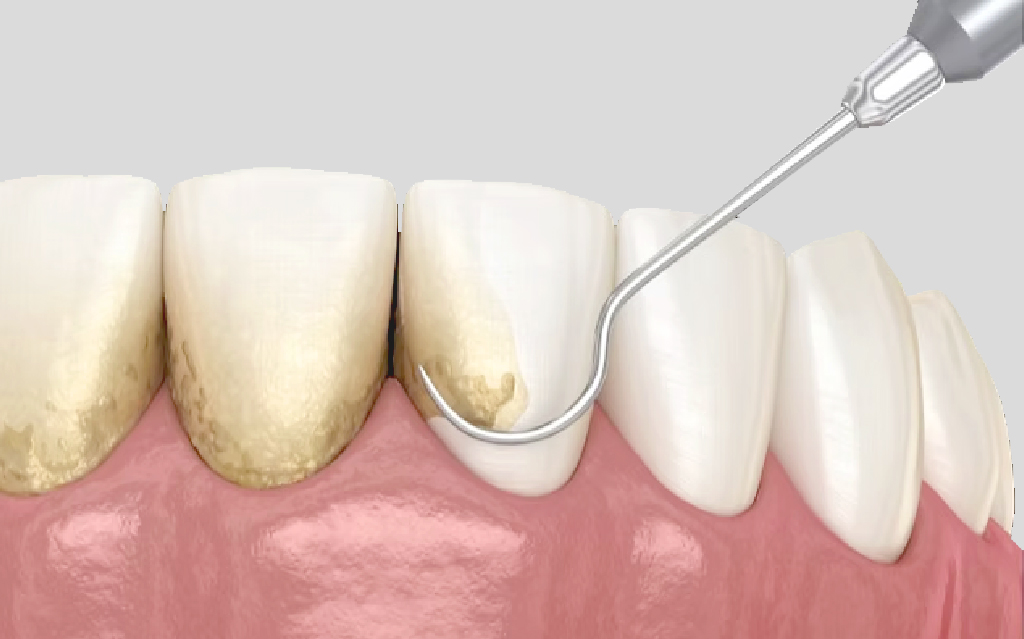

牙周病治療 – 非手術性治療

會以超音波洗牙機頭與牙周刮刀清除牙根表面的牙結石,並將牙根表面整

平,移除受感染的齒質讓牙周組織重新貼合乾淨的牙根表面。

清除牙結石與牙根整平